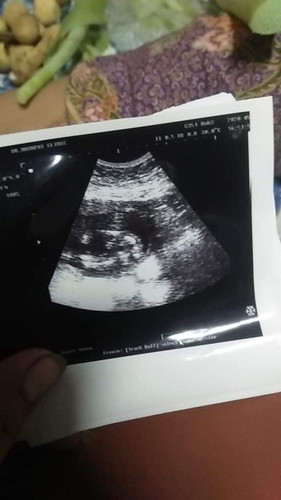

เพศเด็ก

แม่ๆๆดูหน่อยไห้หน่อยได้ไม่ค่ะผู้หญิงหรือผู้ชายค่ะ21สัปดาแล้วค่ะน้องน้ำหนัก433กรัมน้ำหนักปกติไม่ค่ะ

มองไม่ชัดเลยค่ะแม่ หมอไม่บอกหรอค่ะว่าชายหรือหญิง